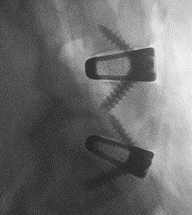

“3D printing provides the opportunity to rethink the way implants can deliver better quality of life for patients in need of spinal fusion,” said Jamie Manos, Centinel Spine Fusion Product Director. “Creating a fully titanium implant with a complex lattice scaffold designed to enable bony on-growth, in-growth and thru-growth, with good imaging properties and a subsidence profile similar to PEEK is something that simply isn’t possible with traditional manufacturing methods, and is a game changer in the interbody space.”

“3D printing provides the opportunity to rethink the way implants can deliver better quality of life for patients in need of spinal fusion,” said Jamie Manos, Centinel Spine Fusion Product Director. “Creating a fully titanium implant with a complex lattice scaffold designed to enable bony on-growth, in-growth and thru-growth, with good imaging properties and a subsidence profile similar to PEEK is something that simply isn’t possible with traditional manufacturing methods, and is a game changer in the interbody space.”